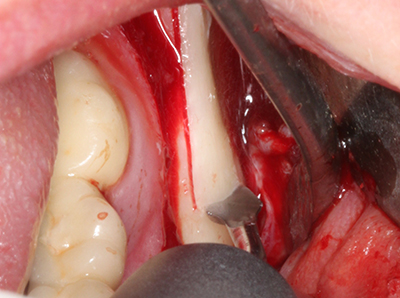

Пиезохирургията има допълнителни предимства при събиране на костни блокове. В допълнение към високата прецизност при остеотомията, описана по-горе, употребата на фините режещи накрайници значително намаляват загубата на материал. Голяма загуба на материал по време на събиране може да се очаква с дебелите накрайници, особено при употреба на борери Линдеман (Lakshmiganthan, Gokulanathan et al. 2012). Базалното разделяне, което е необходимо, особено за присадка на блок при ретромолар, е улеснено от специално създадени правоъгълни триони. В резултат на това, пиезохирургията е разглеждана като прецизна, улеснена и безопасна процедура за събиране на костни блокове в ретромоларното пространство (Happe 2007) (Фиг. 1-12).

Когато се извършват хирургични процедури върху кост в непосредствена близост до чувствителни структури като кръвоносни съдове или нерви, ротиращите инструменти създават значителен риск за ятрогенно нараняване. Пиезоелектрическите апарати могат да бъдат от помощ при препарация на костно покритие и отстраняване на твърда кост близо до нерви, особено за оголване на нервите след ятрогенно нараняване, както и по време на латерализация на нервите за резекционни и реконструктивни процедури или поставяне на имплант (Фиг. 17-20). Лекият контакт между пиезонакрайника и нерва по принцип не води до нараняване, но ако действате непредпазливо с трионообразни движения или приставки за остатъчен костен субстрат, може да причините временно или перманентно увреждане на нерва. Въпреки това, рискът от увреждане се счита за много по-малък, отколкото при употреба на триони или ротиращи инструменти (Pereira, Gealh et al. 2014).